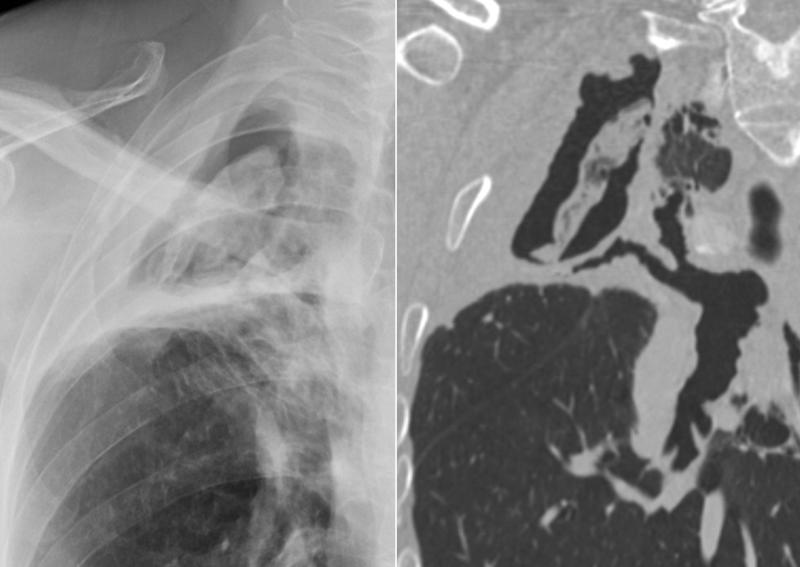

Aspergilloma